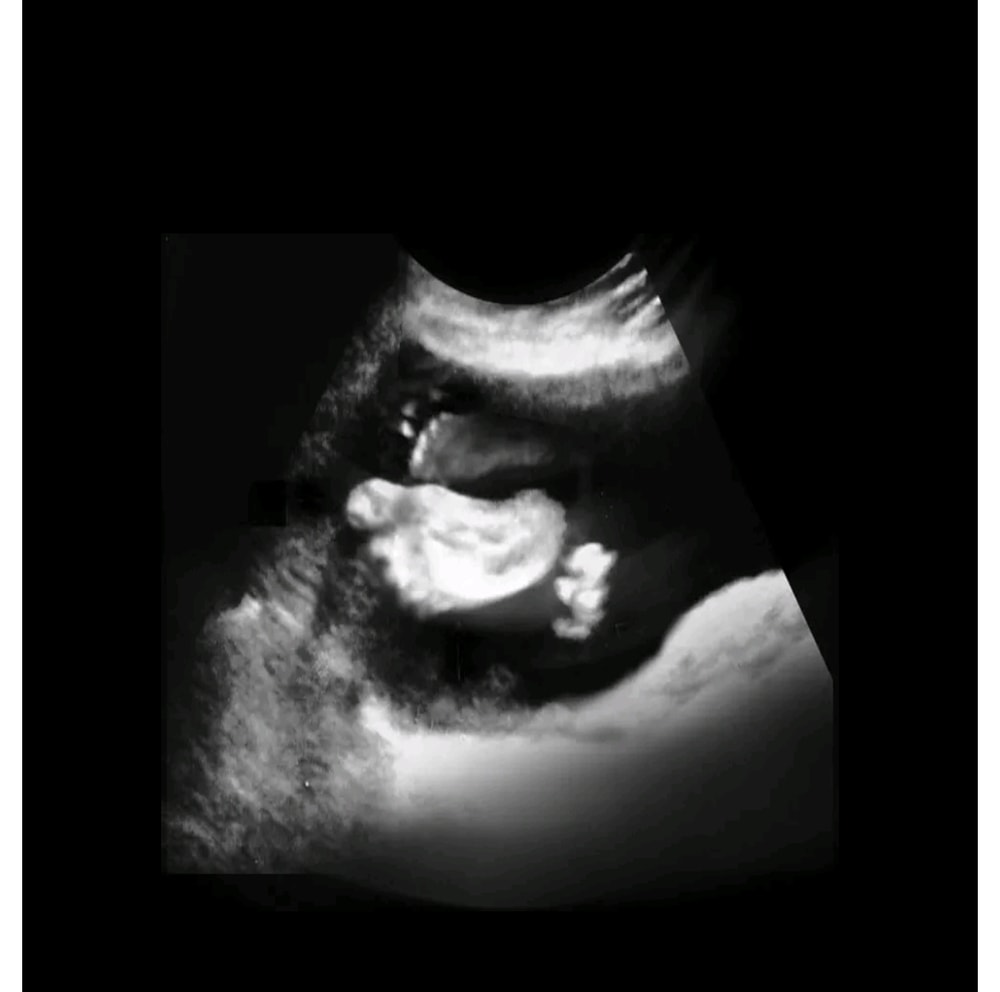

Пол лялечки

Возможно девочка. Не очень понятно. Хорошо виден только тонус.🤷